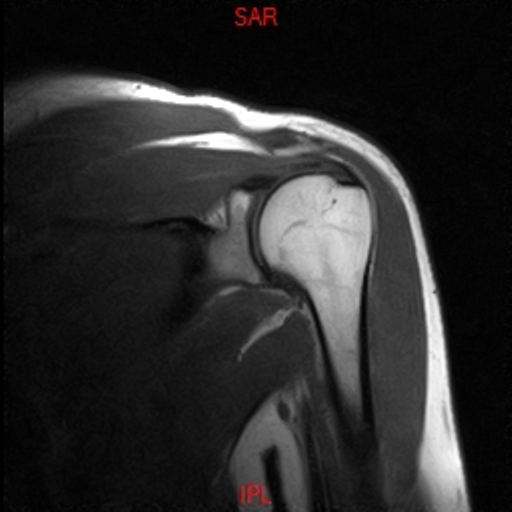

• RESONANCIA PATOLÓGICA DE HOMBRO - FRACTURA TROQUITER -  COR T1